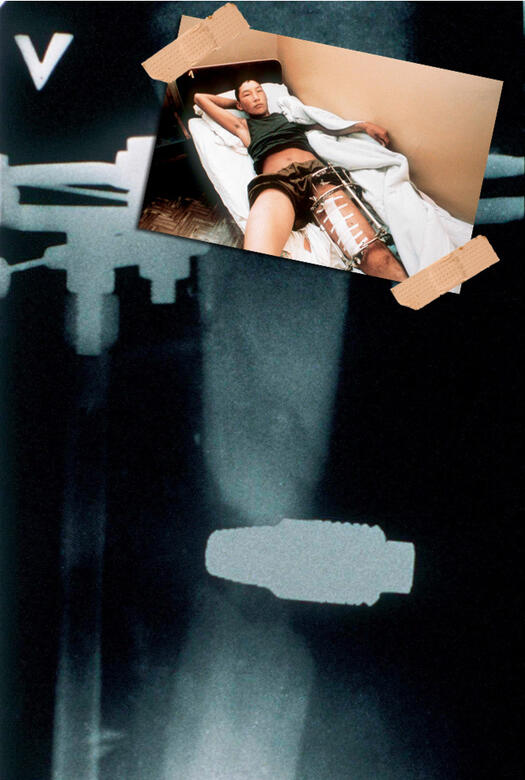

ЕКСПОНАТ 8

Граната

Тук вече няма нищо смешно. 22-годишният Андрей Чободаев, който отбива военната служба в Чечня (доволно отвратително място) – граната от гранатомет го уцелва в крака, но не се взривява, операцията протича под зоркото наблюдение на сапьори. Андрюша е здрав. УРА!